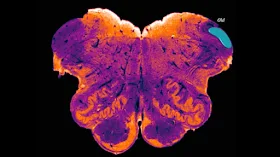

from Neuroscience Research Australia has discovered a hidden region of the human

brain. The endorestiform nucleus is found near the brain-spinal cord junction.

Image credit: George Paxinos, Neuroscience Research Australia.

The Endorestiform

Nucleus was hidden within the inferior cerebellar peduncle. Credit: NeuRA

περιοχή, την οποία ο Γ. Παξινός ονόμασε «Ενδοσχοινιοειδή Πυρήνα» (Endorestiform Nucleus), βρίσκεται κοντά στο σημείο όπου ενώνεται

ο εγκέφαλος με το νωτιαίο μυελό. Συγκεκριμένα, βρίσκεται μέσα στο κάτω

παρεγκεφαλιδικό σκέλος, μια περιοχή που ενσωματώνει και συνδυάζει τις

αισθητηριακές και τις κινητικές πληροφορίες, προκειμένου να διορθώσει τη στάση

του σώματος, την ισορροπία του και τις μικρές επιδέξιες κινήσεις.

Nucleus could play a part in fine motor control. Credit: NeuRA